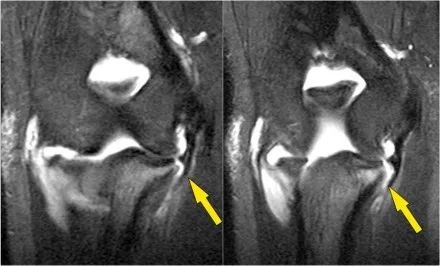

外翻过度综合征的关节病由于外翻过载,在肱骨-尺骨关节的后内侧部分存在剪切力。注意在T1W图像上看到的软骨下硬化(红色箭头)。在T2W图像上存在软骨下骨髓水肿和软骨损失(黄色箭头)。

冠状图像上有一个美丽的UCL前束,但注意到关节内侧部分有骨赘形成(红色箭头)。当我们按照顺序向下看,可以看到存在一小部分低信号强度(黄色箭头),这是UCL的一部分撕裂。